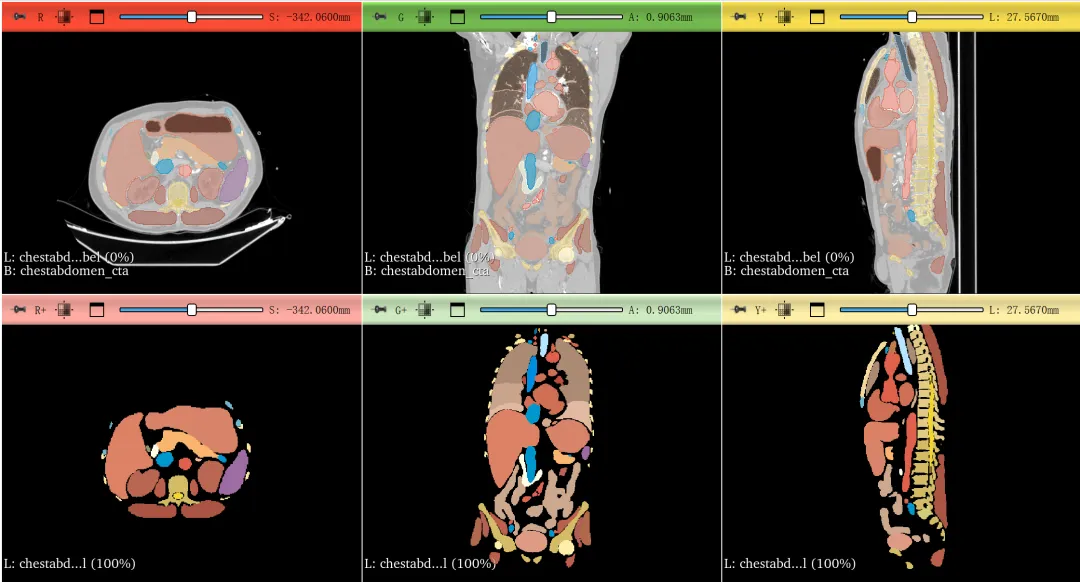

在3D Slicer中,有大量的AI工具可以对全身器官,包括头颈胸腹器官,骨骼,肌肉,脂肪,血管,肺段,肝段等结构进行快速分割。

3D Slicer基础与AI分割工具集:掌握半自动分割与多种AI自动分割工具(MONAI Auto3DSeg、TotalSegmentator、CADS、MONAI label、Dental Segmentator、nnInteractive等),覆盖全身器官、肿瘤和血管。